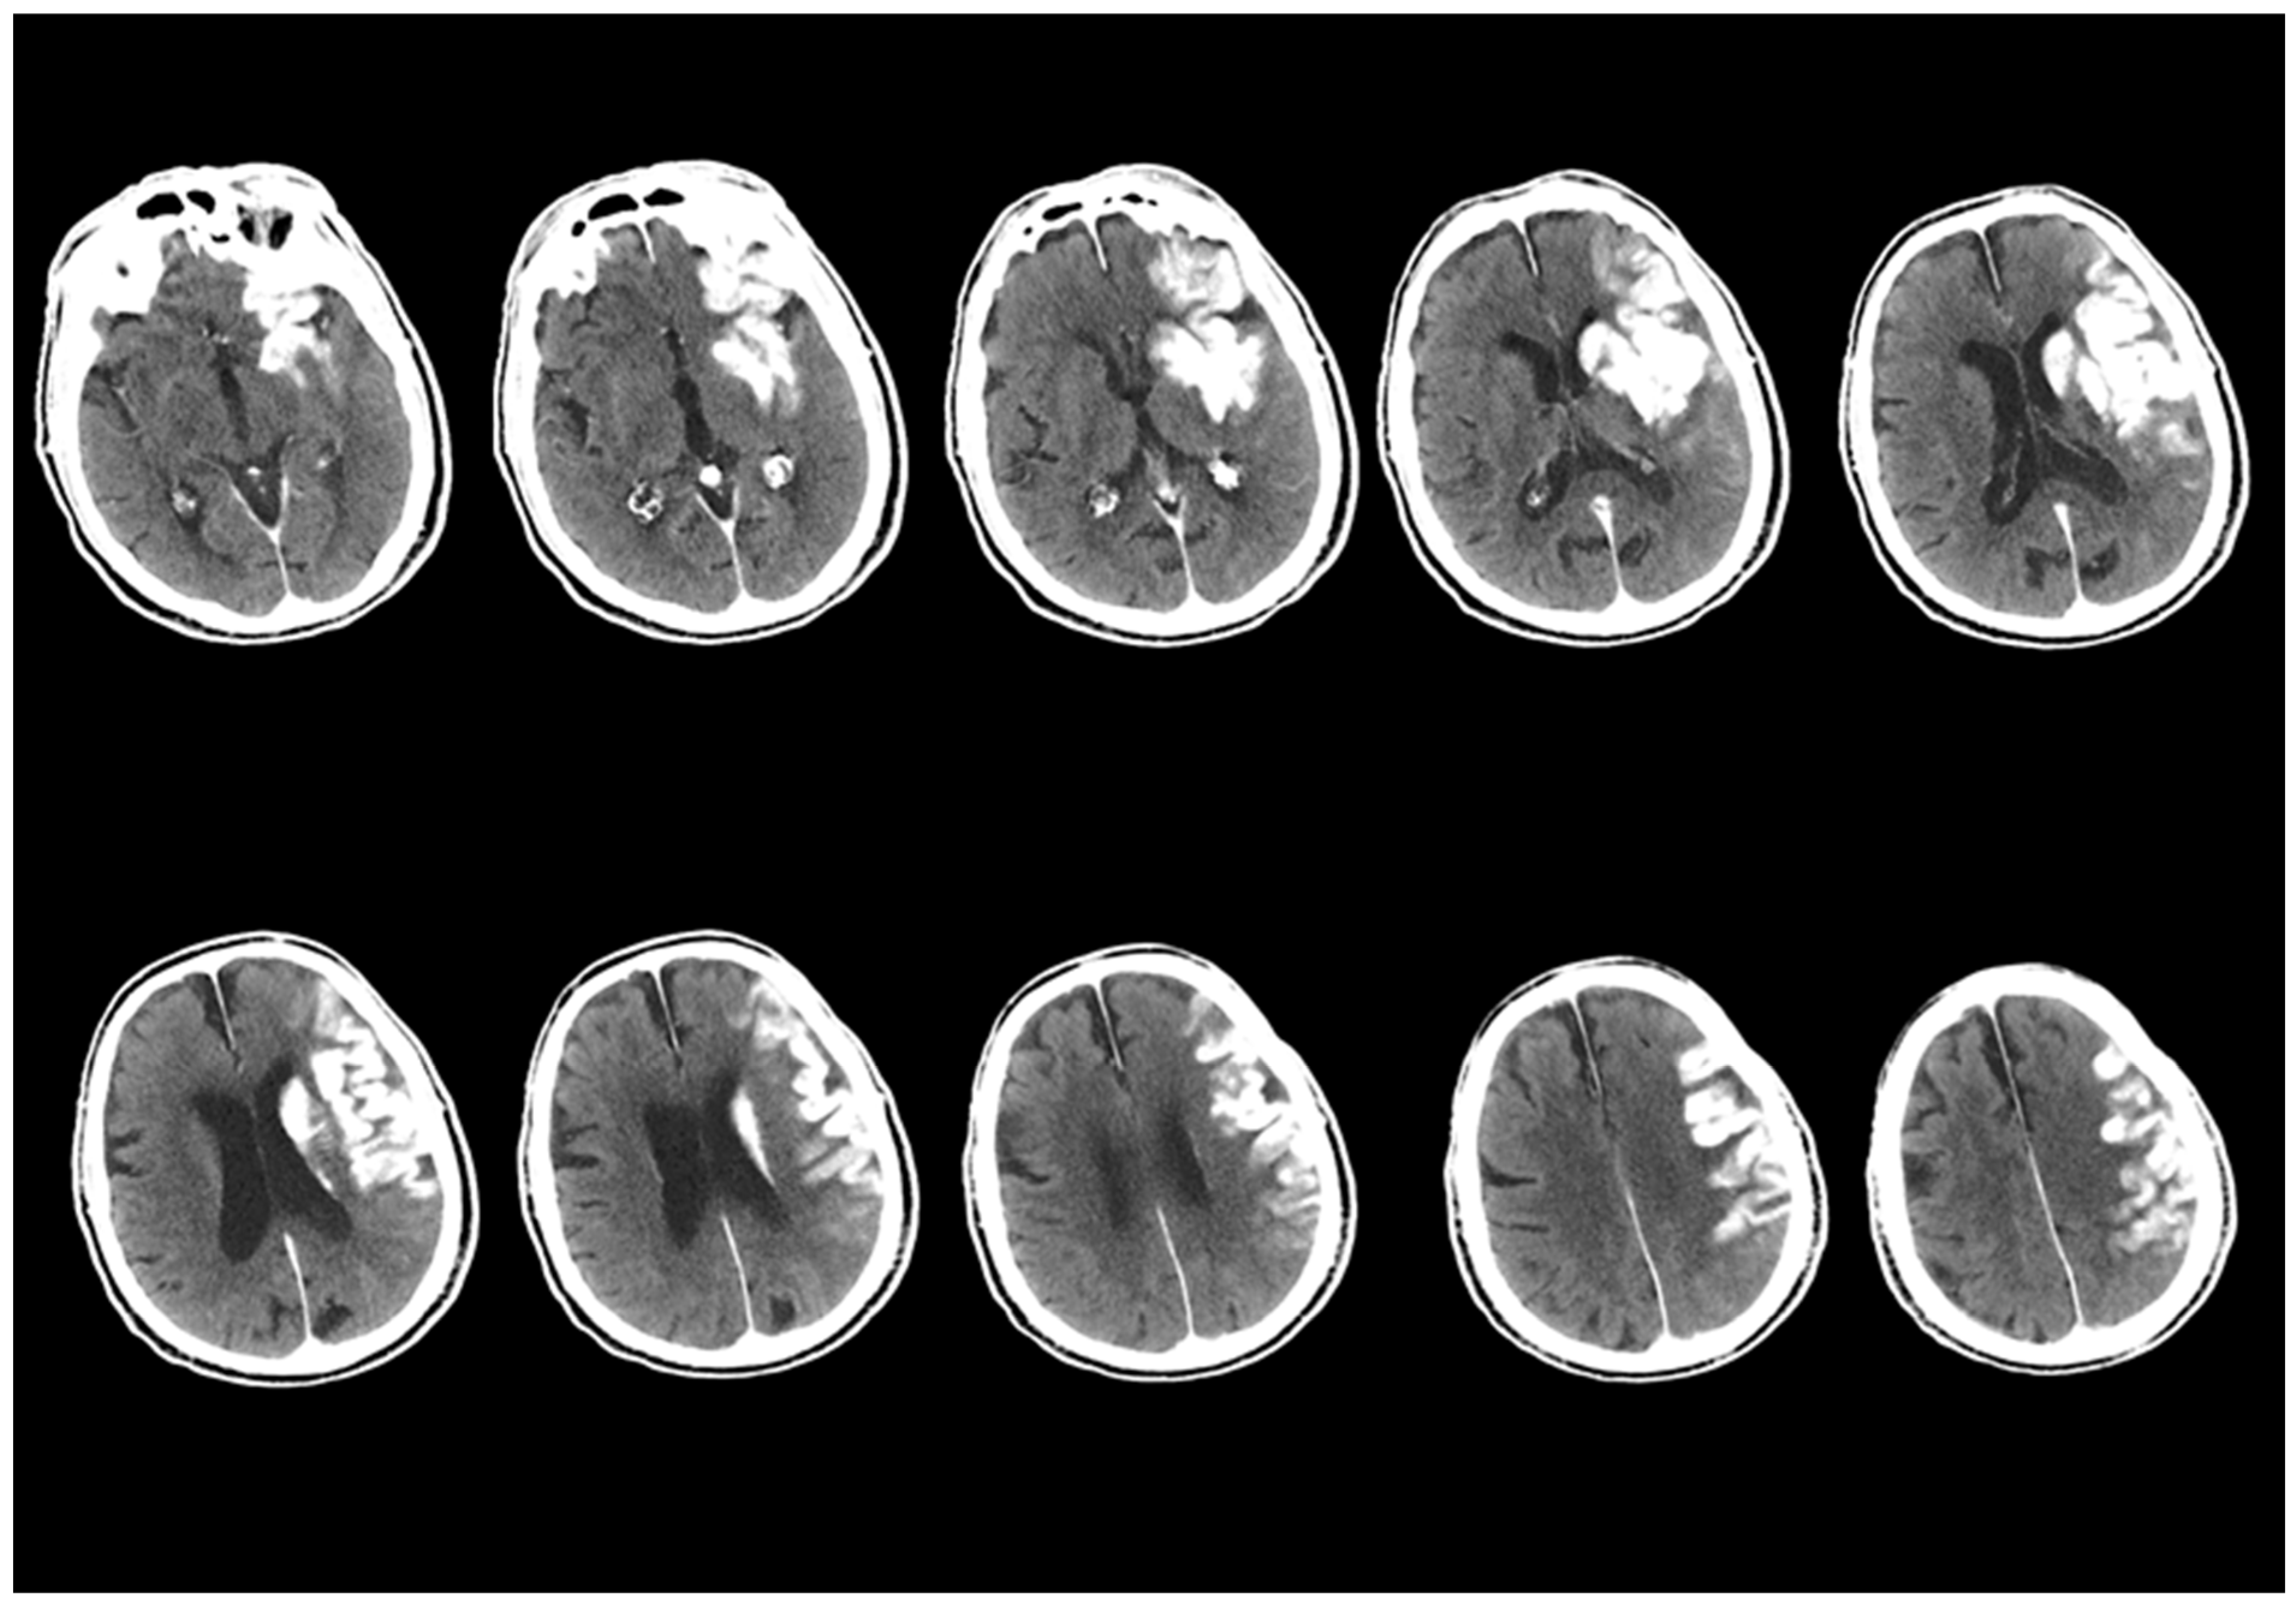

Patients with hyperdensity areas found on NCCT tests within the first 24 h after EVT were designated as having ‘initial NCCT scan’ examinations. NCCT images obtained 24 h after the EVT procedure were designated as ‘follow-up NCCT scans’. These images were analysed retrospectively. The initial and follow-up NCCT images after the EVT procedure were evaluated through a consensus review by two radiologists from the team that performed the EVT procedure (the team leader is an interventional neuroradiologist with 10 years of experience (M.B.) and a board-certified radiologist (E.K.). An example of the evaluated initial NCCT scan images is presented in Figure 1.

Figure 1.

Initial NCCT scans from 12 different patients. Hyperdense areas observed within the first 24 h after EVT are presented, specifically located in the regions where EVT was performed. Two radiologists evaluated changes in the location, size, morphology, and density of these hyperdense areas. Each characteristic was categorized as increasing, decreasing, unchanged, or resolved.

In the study, the first screening of NCCT examinations after EVT procedures was evaluated. The initial NCCT tests were classified into two different groups as ‘contrast accumulation’ or ‘hemorrhagic transformation’ as mentioned above. A dataset containing images in JPEG format and with a resolution of 1920 × 1080 pixels was used for the study. This dataset includes approximately 556 images obtained from a total of 52 different patients. There is an equal number of image data and patient counts in both groups. To enhance classification performance and prevent unnecessary repetitions in the dataset, only slices where the hyperdense area was most clearly visible were selected. During this selection process, slices were included in addition to the slice where the hyperdense area was most intensely located for each patient, taking approximately 5–6 slices above and below. The remaining excess data were removed, making the dataset more focused. The dataset for all patients consisted of approximately 9–13 slices where the hyperdense area was most clearly visible, with a slice acquisition interval of 5 mm. An example of the files composed of these images is shown in Figure 4. Subsequently, the images of all patients were organized and filed separately for each patient.

Figure 4.

An example of the first scan used in the dataset, the NCCT scan, is shown. The images from the NCCT examination taken within the first 24 h after the EVT procedure of an 87-year-old male patient with a left MCA M1 occlusion include images obtained from approximately 5–6 slices above and below the slice where the hyperdense area is best visualized, with a 5 mm slice acquisition interval.